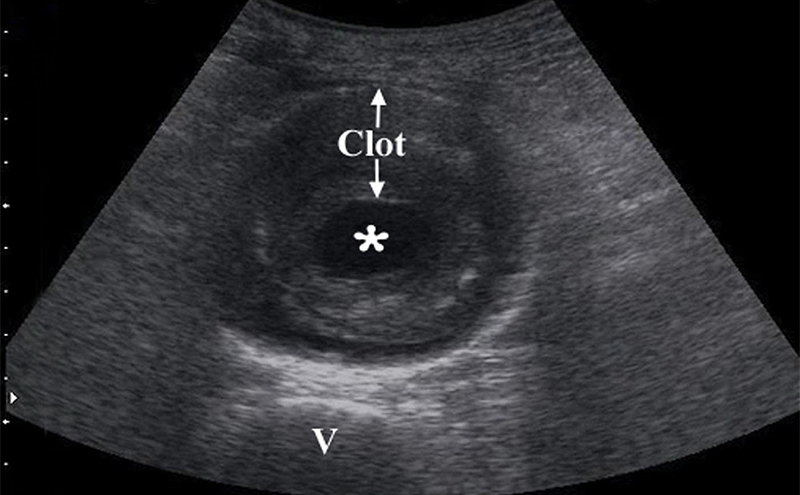

- Obtain measurements of aorta from outer wall to outer wall. Since aneurysms will often contain a thrombus, and with time this becomes calcified and hyperechoic, one may accidentally mistake the inner rim of the thrombus for the aortic wall. Doing this will lead a falsely decreased measurement of the true aortic diameter, possible causing the aneurysm to be missed completely.

- Figure 9. Transverse view of a 7 cm AAA with intraluminal clot (* on the lumen, “v” denotes vertebral body)